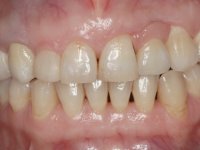

• Confeção e colagem de uma nova faceta feldspática para substituir a fraturada. A nova faceta deverá incluir maior área dentária inter-proximal distal do dente 2.1.

• Substituir a faceta do dente 1.2 por uma coroa total em cerâmica feldspática ou por uma, agora denominada, faceta 360.

O tratamento iniciou-se com a re -preparação do coto do espigão falso coto fundido, com o objetivo de colocar as linhas de acabamento cervical com uma localização intra-sulcular e simultaneamente confecionar uma coroa provisória adaptada. Com um tratamento ortodôntico muito simples, fechou-se o diastema entre os incisivos centrais superiores e estabilizou-se esta posição com um arame colocado na superfície palatina dos centrais, funcionando como contenção. Posteriormente procurou-se fazer uma tração ortodôntica lenta do dente 2.2 com o intuito de diminuir, ainda que muito ligeiramente a perda óssea vertical nessa zona. Finalizada a tração, foi feita a extração do dente 2.2 e a zona foi reabilitada provisoriamente com uma coroa de resina composta colada aos dentes adjacentes. Foi colocado um implante dentário na zona do dente 2.2 sendo novamente colada a coroa provisória em resina, reabilitando provisoriamente a paciente durante o período de osseointegração. No dente 1.3 foi feita uma gengivectomia com bisturi elétrico, com a intenção de subir o nível cervical do 1.3 conseguindo uma maior harmonia com o dente 2.3. Estabilizados os tecidos moles, foi feita uma impressão com a técnica de moldeira aberta, utilizando silicones de adição de consistência “putty” e “light”. A recolha da cor, tanto da componente dentária como dos tecidos moles foi feita pelo ceramista no consultório.  No laboratório as impressões foram passadas a gesso e deram origem a modelos de trabalho que foram devidamente analisados. Foi decidido confecionar um “abutment” metalo-cerâmico aparafusado sobre o implante. Este “abutment” foi fundido com uma liga nobre e posteriormente revestido a cerâmica coronária e gengival. Dada a inclinação do implante o aparafusamento condicionou de forma inevitável a saída do orifício do parafuso pela superfície vestibular. No sentido de esconder esta situação, o desenho do “abutment” já foi idealizado com a intenção de acomodar na superfície vestibular a colagem de uma faceta feldspática. Este “abutment” foi provado em boca e foram feitos ajustes no componente cerâmico gengival. A sua adaptação aos tecidos moles foi feita tanto de forma subtrativa, com broca, como de forma aditiva, acrescentando resina composta de tonalidade gengival. Este acrescento de resina seria orientador do ceramista na colocação final da cerâmica de tonalidade gengival. A coroa que reabilitaria o dente 1.3 foi cimentada nesta consulta de prova com cimento de ionómero de vidro reforçado com resina composta. Finalizado o trabalho em laboratório da faceta sobre o 1.2 e o “abutment” e a faceta para o implante este foi colado em boca, após a colocação do isolamento absoluto. O trabalho satisfez plenamente a paciente. Durante oito anos a paciente foi seguida regularmente, mostrando-se agradada com o tratamento efetuado, no entanto começou a mostrar interesse em intervir esteticamente nos incisivos centrais superiores. Decidida a segunda fase da nossa intervenção, foi feita a preparação dentária dos dentes 1.1 e 2.1 para a colocação de duas facetas feldspáticas. Particular cuidado foi tido na preparação inter-proximal distal junto ao “abutment” do implante. Foi preciso avaliar muito pormenorizadamente o eixo de inserção da faceta em relação ao “abutment”. As facetas feldspáticas foram confecionadas em laboratório e posteriormente coladas em boca após a colocação de isolamento absoluto. Um ano após, iniciamos a nossa terceira fase de tratamento, após a faceta colada no dente 2.1 ter fraturado. A preparação dentária foi feita sobre a faceta colada, procurando estender mais para palatino o interface inter-proximal distal. O objetivo seria passar para mais palatino do ponto de contacto o interface faceta-dente. O preparo dentário do dente 1.2 também foi muito reduzido, limitando-se a criar um eixo de inserção. Após confecionadas a coroa total e a faceta em laboratório foram coladas em boca. Primeiro foi colada a coroa utilizando-se um isolamento relativo com teflon, posteriormente foi colada a faceta após a colocação do isolamento absoluto. Na coroa utilizei este tipo de isolamento para evitar a utilização de grampos. Seria difícil de aplicar pela forma e dimensão do dente e agressivo para os tecidos moles. Após a colagem foi avaliada a integração oclusal do trabalho.